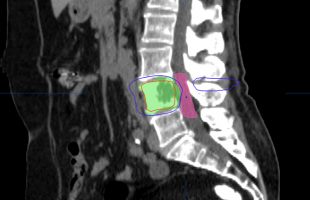

Η Μα. Φο. 26 ετών προ δεκαετίας υποβλήθηκε (αλλαχού) σε χειρουργική επέμβαση στη θωρακο-οσφυική περιοχή της σπονδυλικής στήλης (Σ.Σ.). Η επέμβαση εγένετο προκειμένου να αφαιρεθεί καλοήθης νεοπλασματική εξεργασία (επενδύμωμα) η οποία της είχε προκαλέσει σφιγκτηριακές και νευρολογικές διαταραχές στα κάτω άκρα. Προκειμένου να γίνει εξαίρεση της νεοπλασματικής βλάβης, πραγματοποιήθηκε ευρεία αφαίρεση οπίσθιων στηρικτικών στοιχείων τωνRead more →